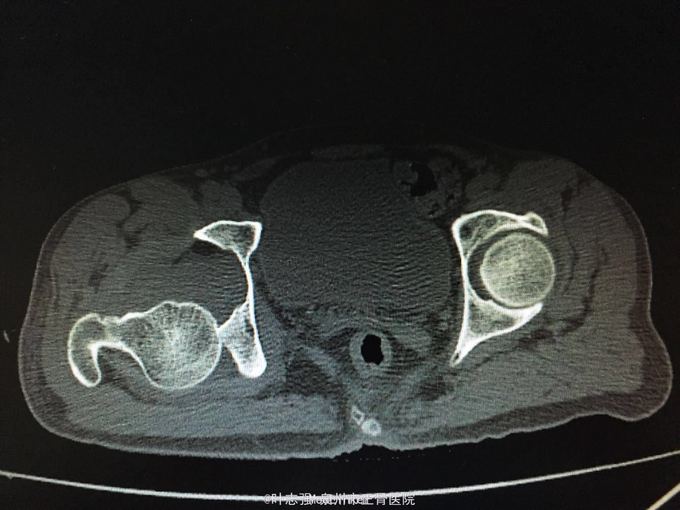

髋臼骨折伴髋关节后脱位ORIF

车祸致左髋部疼痛、活动受限1天。 53岁男性

左髋臼骨折伴髋关节后脱位 行生命支持,股骨髁上骨牵引,